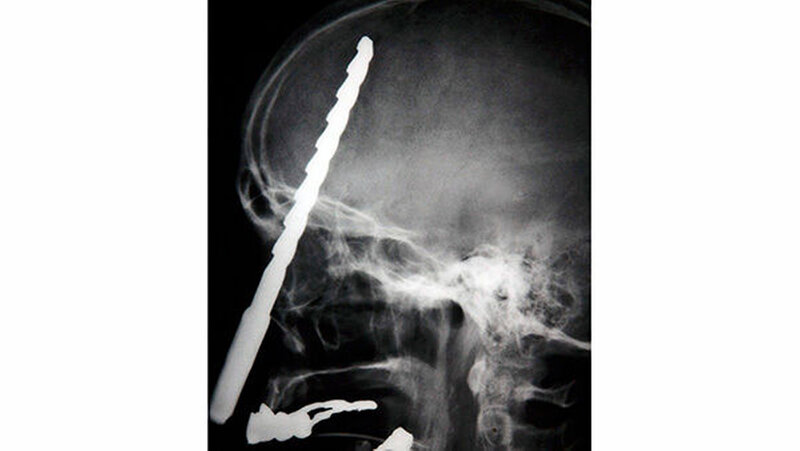

Vom Bohrer im Kopf bis zum Schlüssel in der Kieferhöhle: Die MKG-Chirurgen der Charité haben ausgewählte Patientenfälle mit Fremdkörpern im Gesicht zusammengestellt. In unserer Fotostrecke finden Sie die eindrucksvollen Aufnahmen.